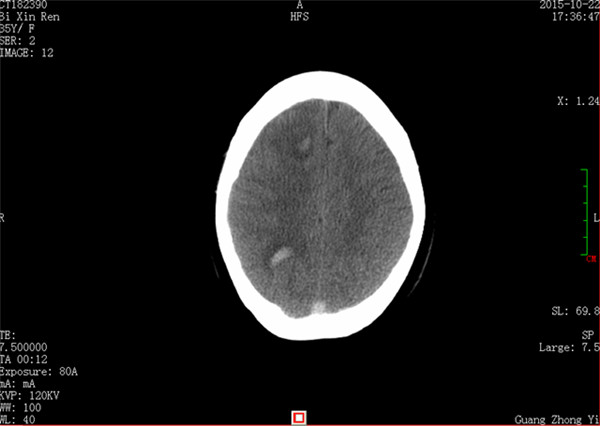

患者闭某,女性,35岁,因产后十余天,进行性头痛就诊收入我科,患者头颅CT证实颅内多发出血灶,静脉窦栓塞可能。患者入院后头痛呈进行性加重,出现反复癫痫,病情危重。我科张高炼主任医师、黄建荣副主任医师查看病人后认为患者属于上矢状窦栓塞,是急性脑卒中的一类,而且已出现梗塞性出血,保守治疗效果极差,既往无血管内治疗的情况下死亡率高达80%以上,即使存活患者也会有严重的神经功能障碍甚至长期昏迷可能,如进病情一步发展,患者势必因颅内高压、梗塞性出血,甚至引起脑疝而导致死亡。

入院CT:脑弥漫点状出血